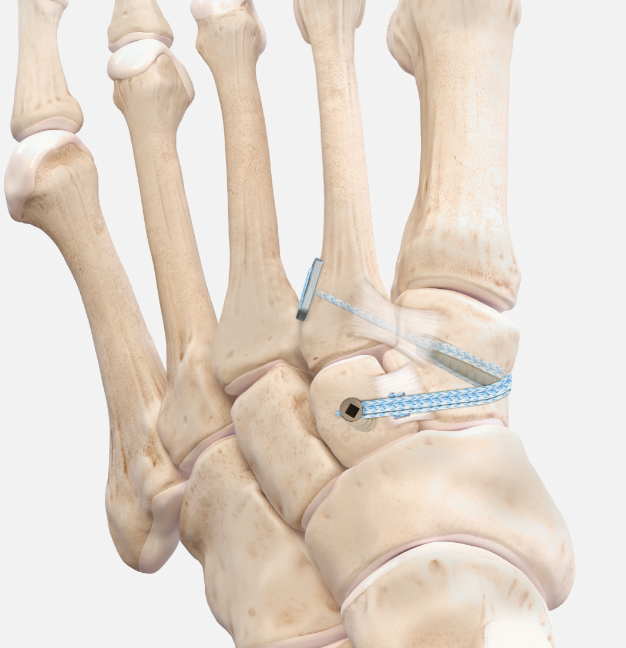

Suture button fixation

Arthrex mini tightrope Lisfranc PDF

Internal Brace

Arthrex internal brace LisFranc PDF

Arthrex internal brace LisFranc video

Vumedi Flexible Fixation Lisfranc injury video